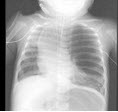

82、单项选择题

女,6月余,呼吸窘迫,左肺呼吸音弱、偶可闻及哮鸣音,结合图像,最可能的诊断()

A.先天性肺气肿

B.细支气管肺炎

C.胸腔积液

D.先天性囊性腺瘤样畸形

E.支气管囊肿